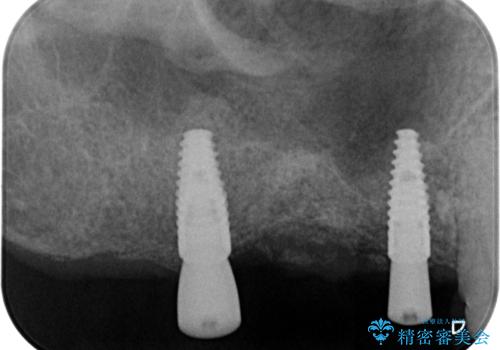

骨の造成を伴う奥歯のインプラント治療

- 破折した歯を放置し、骨が高度に吸収した状態でインプラント治療を希望し来院されました。

インプラントを適切な位置に埋入し仕上げた後にも清掃性を高めるには、必要十分な骨となだらかな歯肉形態の獲得が必要です。

インプラント埋入時に骨の造成を、2次手術時に歯肉の凹みを整え厚みを一定にするような治療を進めていきます。

- 106.7万円 (インプラント×2 アバットメント×2 ジルコニアクラウン×3 骨造成 )費用は治療当時の料金となります

骨の造成、歯肉を整えたことで、術前山形にえぐれていた歯肉形の態はなだらかになり清掃しやすい状態へと整備することができました。